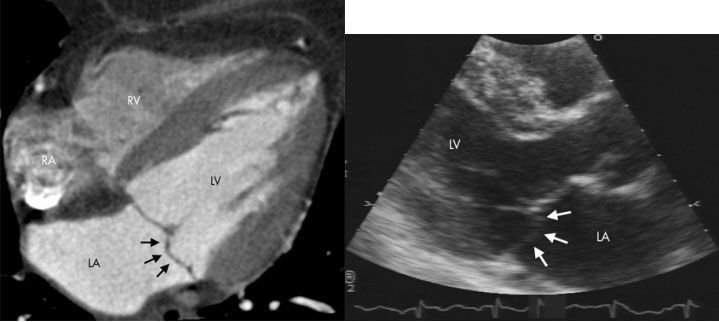

![]() |

| Рис.34. МСКТ сердца по длинной оси (рис. слева) и ЭХОКГ по длинной оси в парастернальной позиции (рис справа). LA-левое предсердие; LV-левый желудочек; RA-правое предсердие; RV-правый желудочек. Пролапс задней створки митрального клапана (стрелки). |

Gerber T.C с соавт (2005г) отметили идентичность диагностических данных при использовании трансторакальной ЭХОКГ и 16 МСКТ в регистрации пролапса задней створки митрального клапана [61] (рис. № 43), Alkadhi H. с соавт. (2006) [62] и Gudrun M. с соавт. (2006) [63] для изучения стеноза аортального клапана. Авторы отмечают 100% чувствительность и 97,3% специфичность МСКТ в диагностике заболеваний клапанного аппарата сердца.

Messika-Zeitoun D. и др.(2006) при сравнении возможностей трансторакальной ЭХОКГ и 16 МСКТ в изучении площади митрального клапана при митральном стенозе указали на более точное измерение и анатомо-визуальное превосходство МСКТ перед ЭХОКГ, и предложили использовать данное исследование у пациентов с плохим ультразвуковым окном или перед протезированием пораженных клапанов [64].